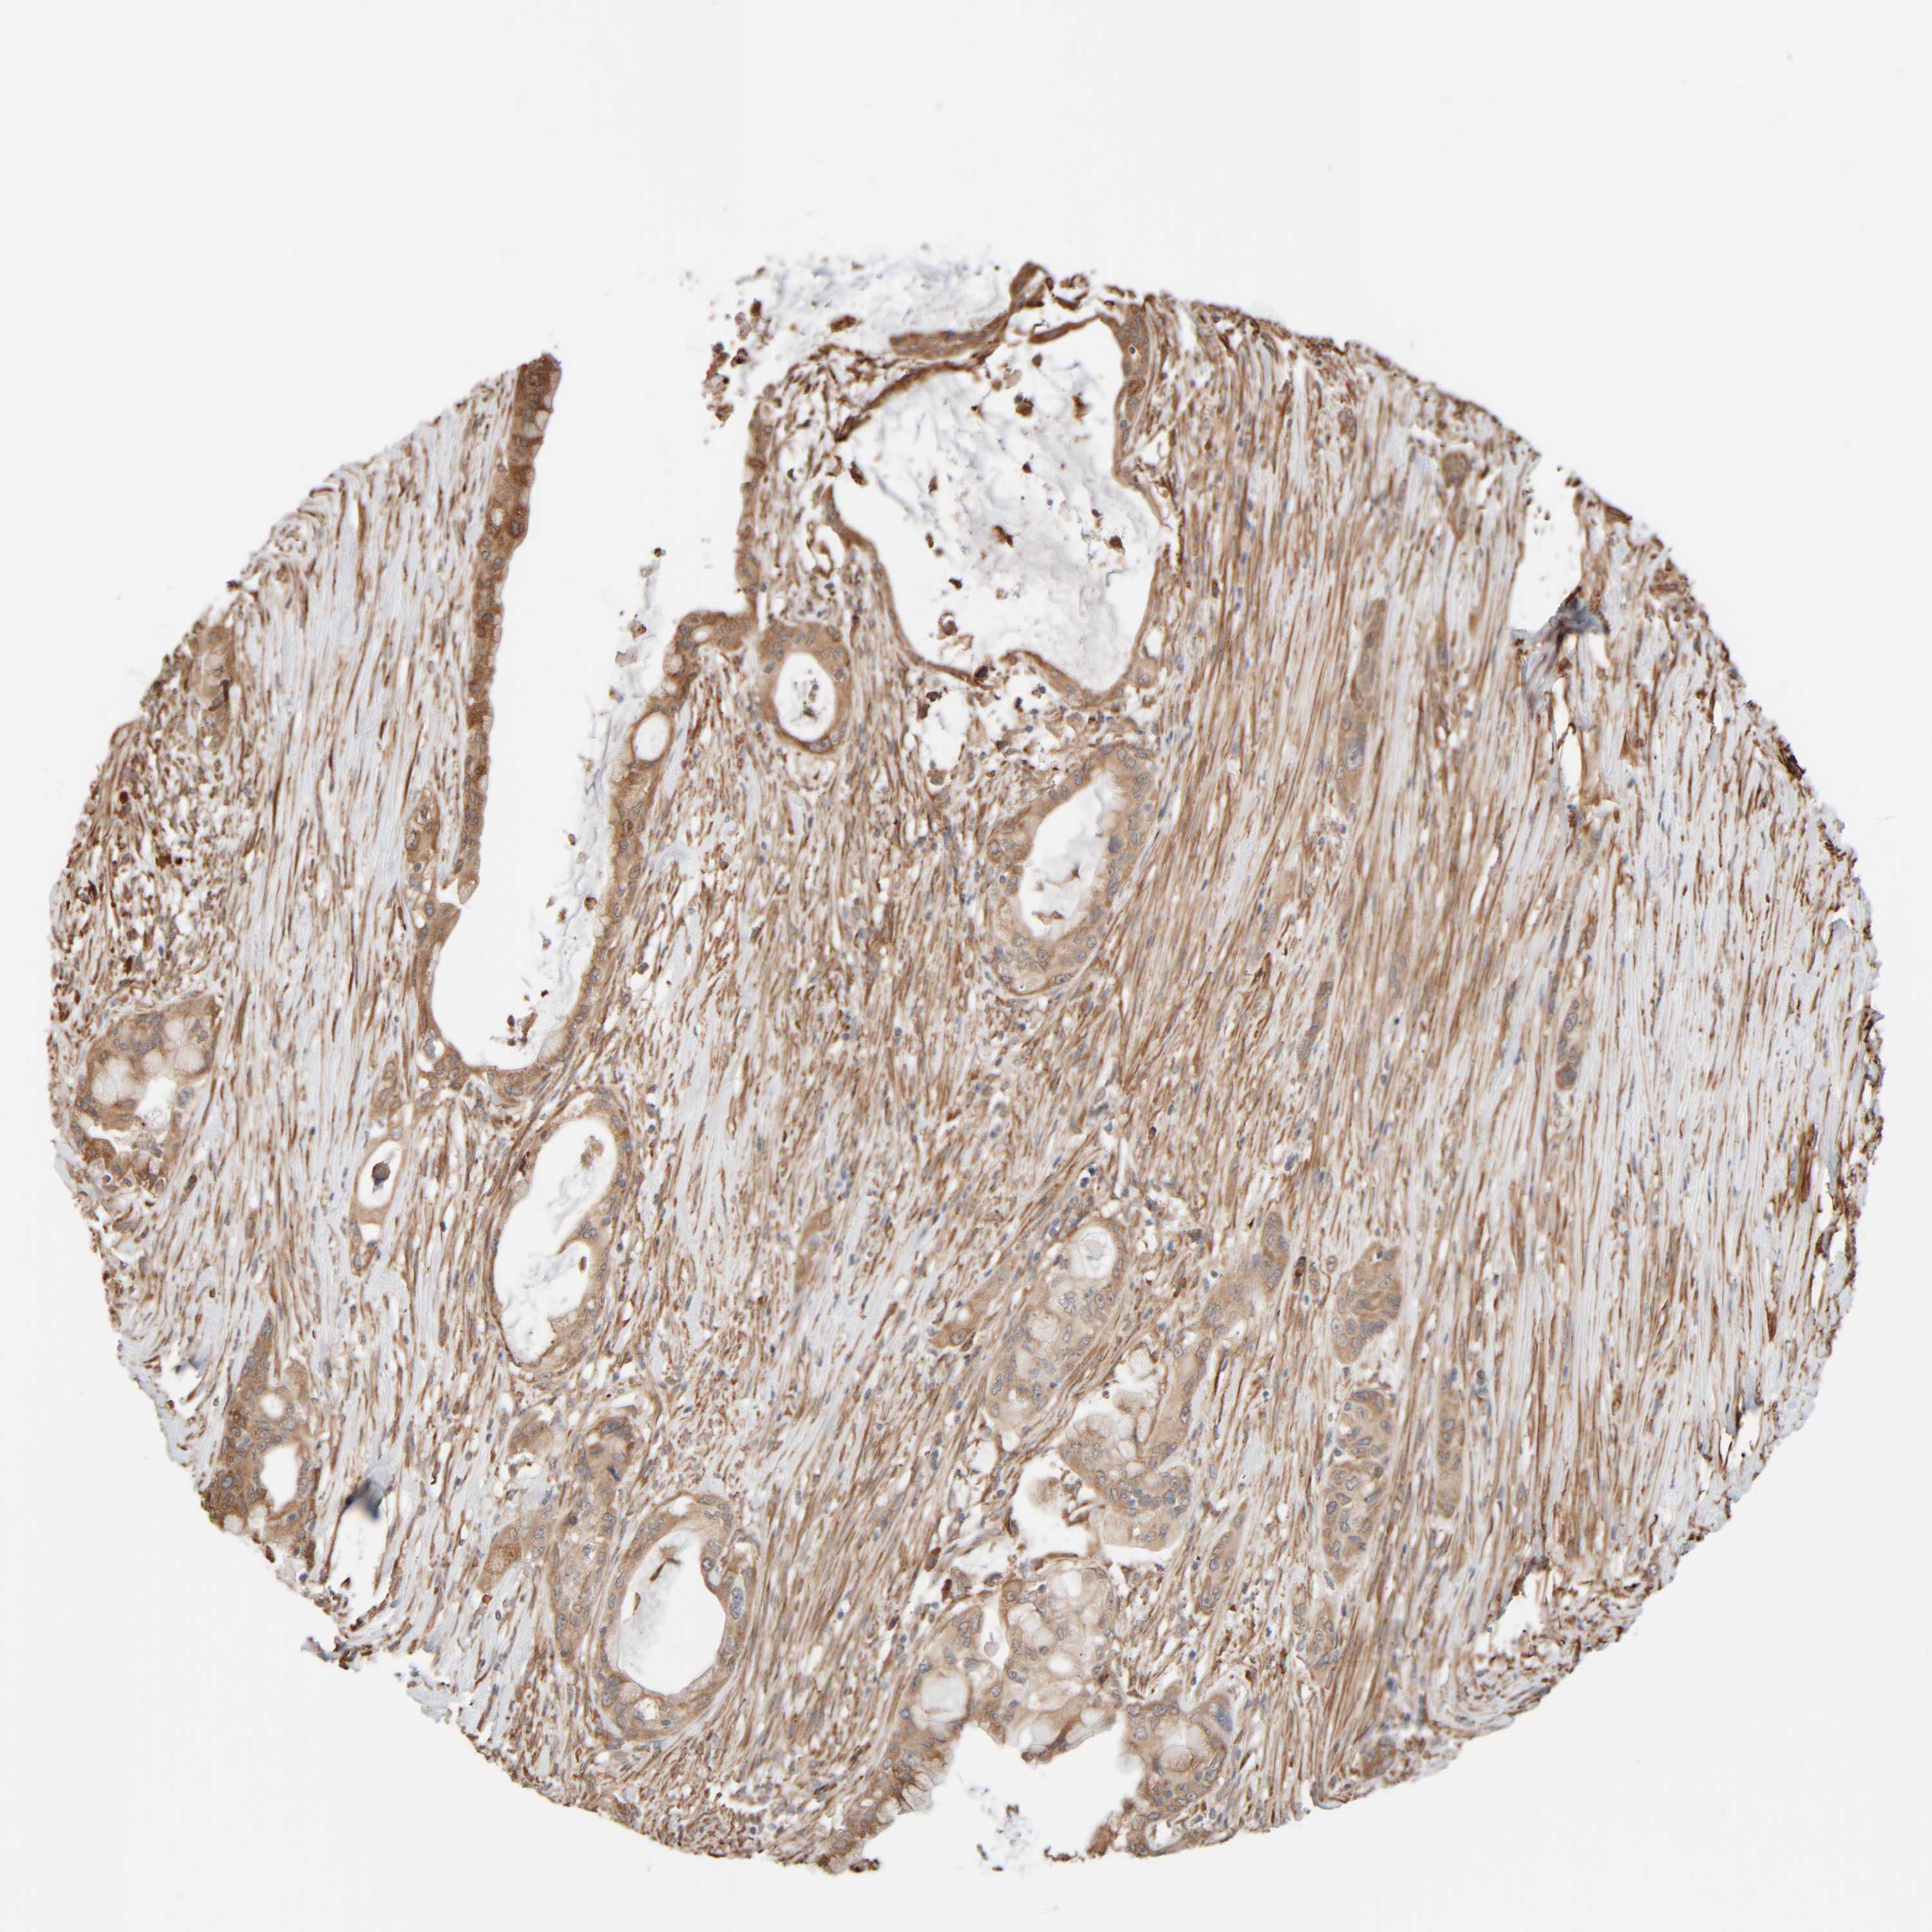

PANCREATIC CANCER - Protein expressioni

A mouse-over function shows sample information and annotation data. Click on an image to view it in a full screen mode. Samples can be filtered based on level of antibody staining by selecting one or several of the following categories: high, medium, low and not detected. The assay and annotation is described here.

Note that samples used for immunohistochemistry by the Human Protein Atlas do not correspond to samples in the TCGA dataset.

Antibody stainingi

Antibody staining in the annotated cell types in the current human tissue is reported as not detected, low, medium, or high, based on conventional immunohistochemistry profiling in selected tissues. This score is based on the combination of the staining intensity and fraction of stained cells.

Each image is clickable and will lead to virtual microscopy that enables deeper exploration of all samples and also displays staining intensity scores, fraction scores and subcellular localization as well as patient and tissue information for each sample.

Antibody HPA021658

Staining

High

Medium

Low

Not detected

Intensity

Strong

Moderate

Weak

Negative

Quantity

>75%

75%-25%

<25%

None

Location

Nuclear

Cytoplasmic/membranous

Cytoplasmic/membranous,nuclear

Adenocarcinoma, NOS